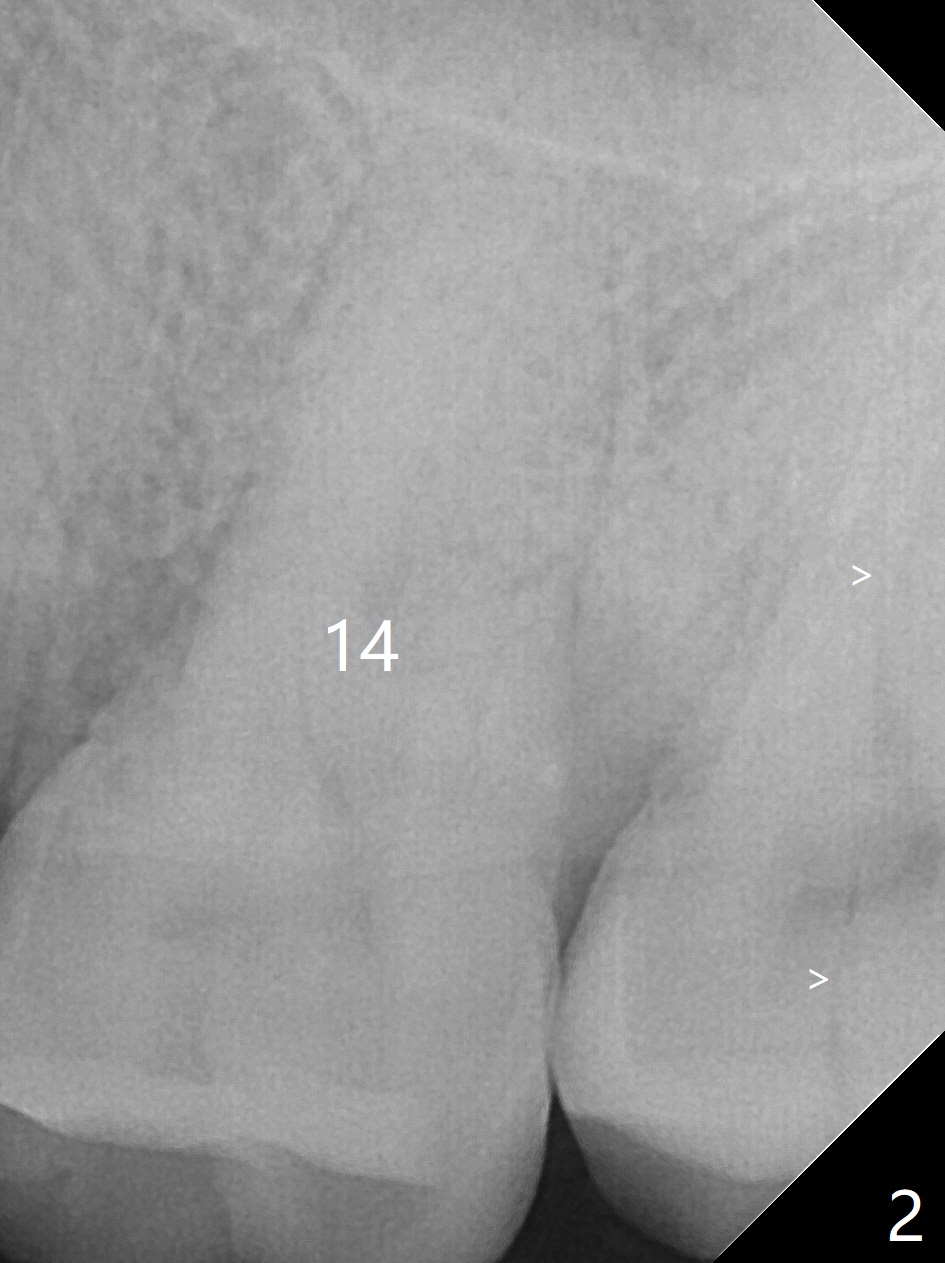

A 44-year-old man presented to clinic with pain of the upper left quadrant (Fig.1), but the affected tooth was not determined until 5 months later (Fig.3,4). Retrospectively the minor crack is visible earlier (Fig.2 arrowheads). It appears that the remaining bone (sinus floor) is limited (Fig.5). Magic Sinus lift or Magic Expanders will be used for sinus lift. Prepare 2-3 pieces of PRF membranes: one or two for sinus lift; the third one to close the socket if primary stability is <30 Ncm.